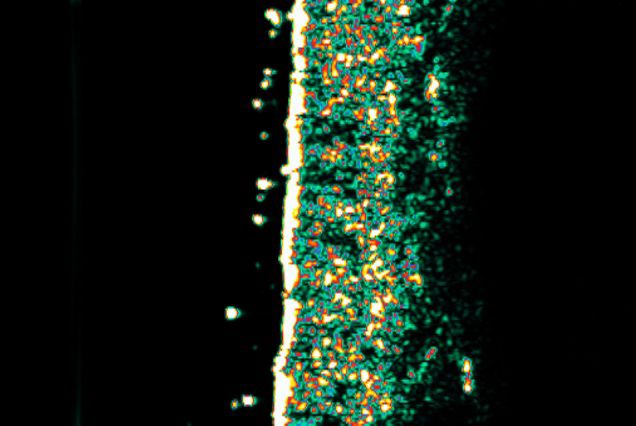

Dopo 15 giorni di trattamento; le zone bianche rappresentano un aumento della produzione di collagene.

Dopo 30 giorni di trattamento; l’analisi mostra una produzione significativa di collagene.

30%

Aumento di oltre il 30% di produzione di collagene

19.6%

Aumento di oltre il 19,6% di elasticità cutanea

11.6%

Riduzione di oltre l’11,6% della visibilità delle rughe

11.1%

Aumento di oltre l’11,1% di luminosità della pelle